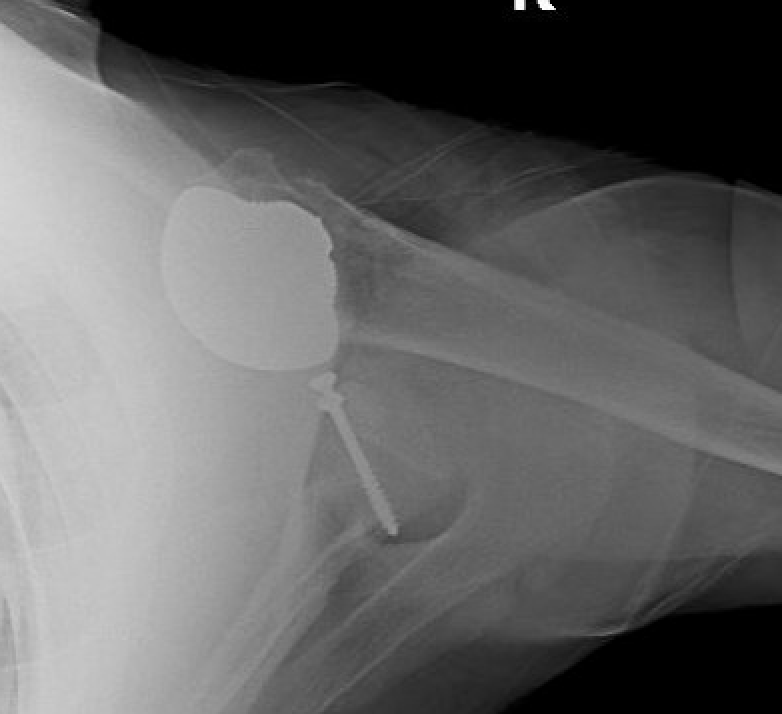

Humeral head replacement + glenoid autograft + rotator cuff repair

Post humeral head replacement / glenoid autograft / rotator cuff repair

Rotator cuff failure and development of anterosuperior escape